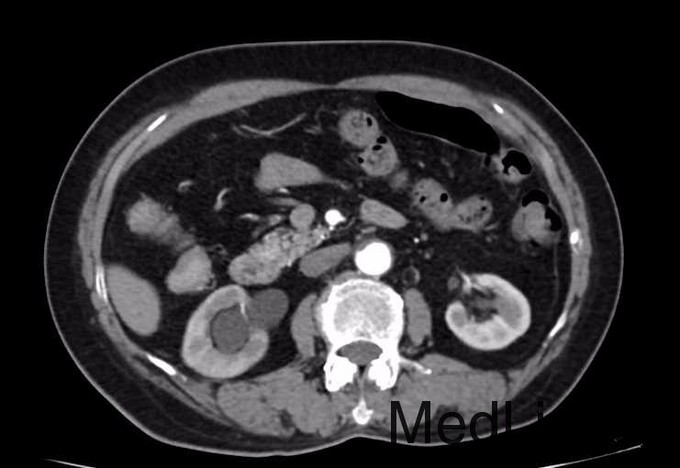

患者女,76岁,主因“腰痛4年,体检发现右肾积水2月余”收入院。 患者诉四年前无明显诱因出现右侧腰部疼痛,为钝痛,未予重视,直至今年8月份突发尿频症状,每天10余次,尿色正常,无尿痛,在海军总院体检发现右侧肾积水;我院CT提示:1、右输尿管中下段有软组织影,考虑占位性变,近端输尿管及肾盂肾盏处积水扩张,2、胆囊结石。今患者为求进一步诊治,遂来我科就诊,门诊以“输尿管占位性病变”收入住院